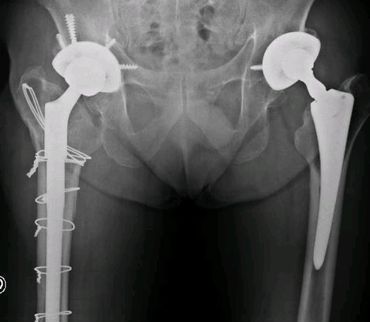

Revisión de cadera en un tiempo quirúrgico, por fractura periprotésica. Tallo de fijación distal, modular, osteosíntesis con lazadas de alambre y coti